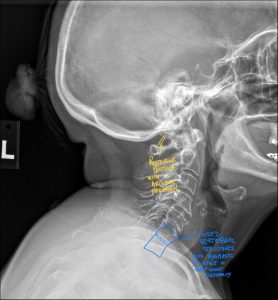

The Role of a Second Opinion Radiology Report

While chiropractors have sufficient training in interpreting X-rays, many chiropractors rely on chiropractic radiology second opinions to provide clear, concise radiology reports to ensure that you receive the best healthcare possible. Your X-rays will be reviewed by a board-certified chiropractic radiologist (DACBR), who can provide a detailed report, and outline the nature and extent of any abnormalities that may or may not change your treatment plan. In cases of diagnostic uncertainty, a second opinion can offer a fresh perspective and added confidence in the diagnosis and treatment plan.